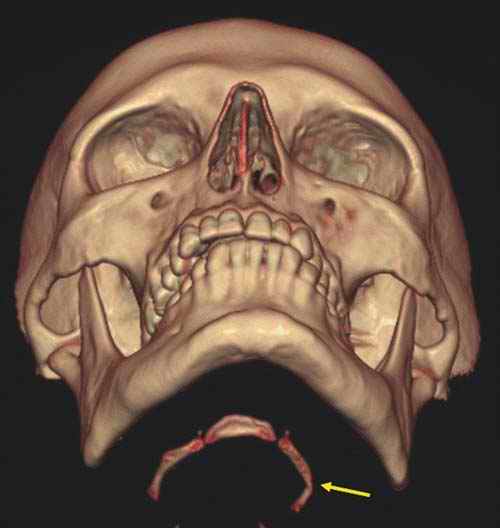

Of these, the fracture of the nasal skeleton is the most frequently encountered. Although generally a self-limiting lesion with little or no danger to the individuals' life or general health, nasal fractures can lead to the suspicion of an involvement of a third party in otherwise inconspicuous conditions. If an otherwise unharmed body of a young man is found in a locked flat with signs of a nasal fracture, then further investigations must be undertaken, even if the presence of a perpetrator at the time of death can be excluded. As the nasal fracture is a possible sign of a prior fight, an autopsy must be performed to examine the possibility of further, externally unseen lesions. However, a nasal fracture may be missed at external inspection. As a dissection of the face leads to disfigurement, the pathologist often refrains from this procedure. Therefore, the nasal fracture may even be missed after an otherwise complete autopsy has been performed. Postmortem multislice computed tomography (MSCT) easily detects such possibly telltale fractures (Figure D3.2.7).

As is well known from clinical medicine, mid-face fractures can also extend over the maxilla and the zygomatic bone (Figure D3.2.8). These fractures arise from a direct impact to the face. Depending on the involved structures, these fractures are classified as Le Fort I-III. This classification can be difficult, especially in cases of vehicle accidents, where, due to the massive damage, multiple fractures are often seen. In such cases, the Le Fort classes overlap (Figure D3.2.9). Mandibular fractures occur due to punches, falls, and vehicle accidents, to name just a few mechanisms. Direct fractures are seen paramedially, whereas indirect fractures are mostly located in the region of the joint and the mandibular body.

Postmortem imaging can display such possibly telltale injuries in a rapid and nondestructive manner, thus sparing the face from further disfigurement or the pathologist from missing a potentially important finding.

![]() |

In cases of strangling or throttling, a limited amount of pressure is exerted onto the cervical vessels, thus giving rise to petechial hemorrhages. However, they are rarely encountered in cases of classic suicidal hanging. In these cases, the afferent and efferent blood vessels to the head are typically-if the noose is behind the mandibular angle-equally compressed. Therefore, no petechial hemorrhages are to be expected. Here, a thorough medicolegal inspection can reveal telltale imprints to the neck, even if the noose has been removed. Slight and superficial abrasions of the skin can often lead to the correct diagnosis. Additional hemorrhages of the subcutaneous tissue and the cervical musculature can, according to our experience, further support this hypothesis (Figure D3.2.18), although recent literature is uncertain as to the overall significance [17,18]. Furthermore, fractures of the hyoid bone or thyroid horns, a finding easily detected in postmortem MSCT (Figure D3.2.19 and Figure D3.2.20), give rise to the diagnosis blunt trauma to the neck [19,20].